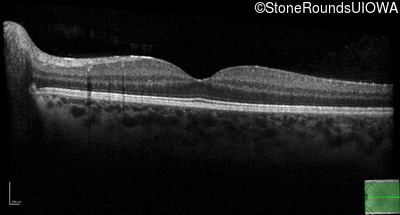

Optical Coherence Tomography - Right - 20/25

Exemplar / OCT Stack